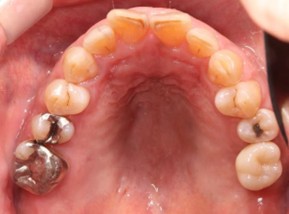

20代 男性

治療前

治療後

治療後- リスク・副作用

(薬・注射・レントゲン・CT・データ分析・骨造成・サージカルステント・血液検査・仮歯) - 年齢/性別

- 20代/男性

- 患者の具体的な症状

- 1年前に左上12 右上1の根の治療をし、その後放置していたら、左上2が破折した。

左上2インプラント補綴 左上1右上1オールセラミック装着。

歯根破折と虫歯による痛み、審美障害を主訴として来院。 - 検査方法

- コーンビームCT、レントゲン撮影

- 診断結果

- 左上2 歯根破折

- 治療詳細

- 左上抜歯後、インプラント埋入1本

骨造成あり 局所麻酔

インプラント治療後、左上1右上1セラミック修復2本 - 通院回数

- 9回

- 治療期間

- 12か月